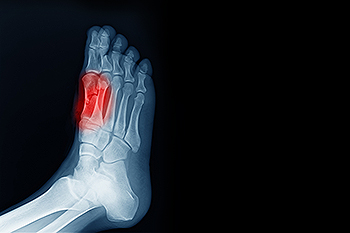

An injury can lead to the foot condition known as sesamoiditis. This can happen as a result of a sporting mishap, which can affect the sesamoid bones that are found inside a tendon or muscle. The sesamoid bones aid with shock absorption, and help in balancing while walking or running. Common symptoms that people can experience with this foot condition can include a dull pain in the bottom or ball of the foot, and they may feel a sensation of stepping on marbles or small pebbles. Bruising and swelling can develop at the site of the injury, and the affected area may be tender to touch. X-rays can aid in the diagnosis of sesadmoiditis, as well as an MRI, which can provide additional pictures of the tissues and tendons surrounding the sesamoid bones. Patients who have sesamoiditis may find relief when supportive shoes are worn, and specific exercises are practiced. This is a condition that is treated by a podiatrist, and it is advised that you schedule an appointment with this type of doctor if you are affected by this ailment.

Sesamoiditis is a condition of the foot that affects the ball of the foot. It is more common in younger people than it is in older people. It can also occur with people who have begun a new exercise program, since their bodies are adjusting to the new physical regimen. Pain may also be caused by the inflammation of tendons surrounding the bones. It is important to seek treatment in its early stages because if you ignore the pain, this condition can lead to more serious problems such as severe irritation and bone fractures.